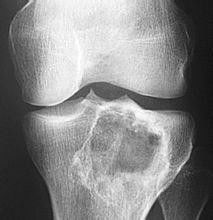

骨肉瘤——骨骼系统恶性程度最高的肿瘤骨肉瘤,作为一种骨骼系统中的恶性肿瘤,其恶性程度之高,对患者的生命健康构成了严重威胁。本文将详细介绍骨肉瘤的相关知识,包括其特点、治疗方法以及预防措施。骨肉瘤,全称为骨原性肉瘤,是一种起源于骨骼间充质细胞的恶性肿瘤。它好发于青少年,尤...